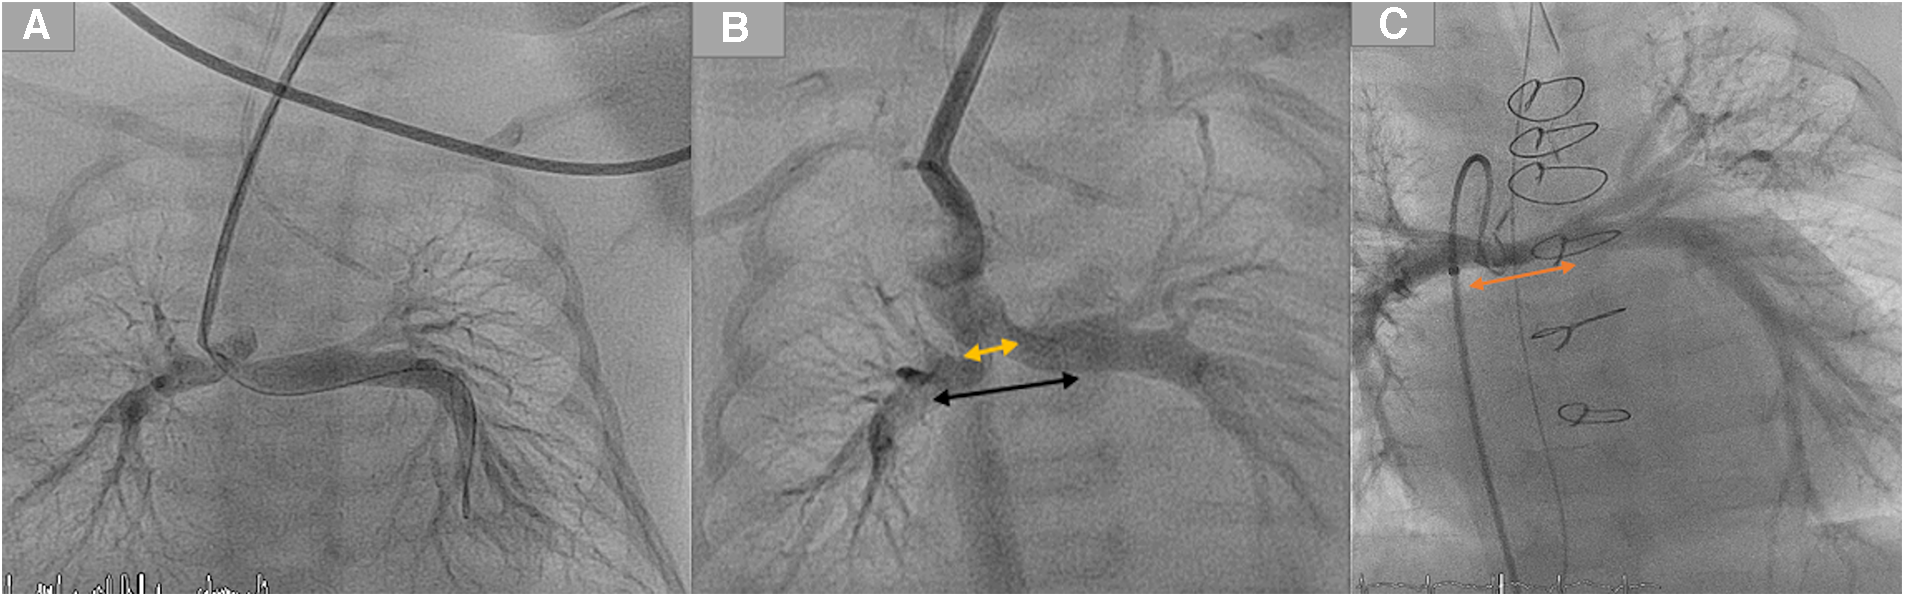

Figure 5

Demonstration of different types of tortuous ducts in patients with duct dependent pulmonary circulation which would be candidates for surgical options.